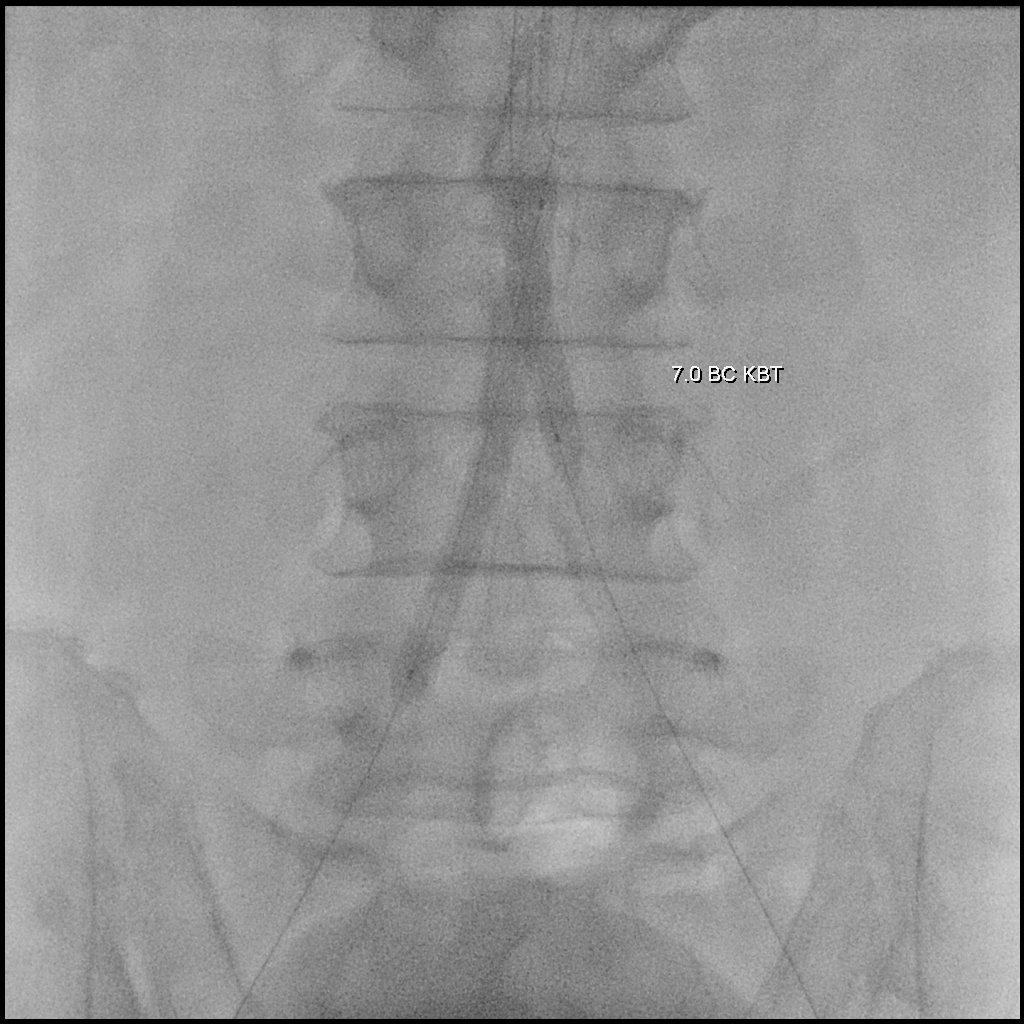

A 6F Mach1 MP guiding catheter waspositioned via aterial access. Wiring was performed sequentially with Gladius0.014¡È and Halberd 0.014¡È under NaviCross 0.018¡È catheter support, then switched to an Astato XS 40 for bettercontrol. Using a CSI microcatheter, the 0.018¡È system was exchanged for a 0.014¡È wire to performIVUS. IVUS initially could not advance but succeeded after predilatation withan Ultraverse 2.0 balloon. IVUS revealed that the lesion was locatedclose to the inferior mesenteric artery and provided accurate vessel sizing forappropriate stent selection. The system was then switched back to the 0.018¡È platform forintervention. Balloon dilatations were performed using Ultraverse 5.0 ¡¿ 80 mmfor the right and 7.0 ¡¿ 40 mm for the left common iliac artery, followed bysimultaneous kissing balloon inflation. Further expansion was achieved with Armada8.0 ¡¿ 80 mm balloons. Two VBX 8.0 ¡¿ 59 mm heparin-bonded stent grafts weredeployed in the right and left common iliac arteries. A subintimal flap belowthe right CIA stent edge required an additional VBX 8.0 ¡¿ 39 mm stent.Post-dilatation was performed with a Finestream S Plus 8.0 ¡¿ 40 mm andUltraverse 7.0 ¡¿ 80 mm balloon using the final kissing technique. Final angiography demonstrated well-expandedstents and excellent bilateral flow without residual stenosis or dissection.Both femoral access sites were closed with ProGlide devices, and the leftradial sheath was removed with manual compression.